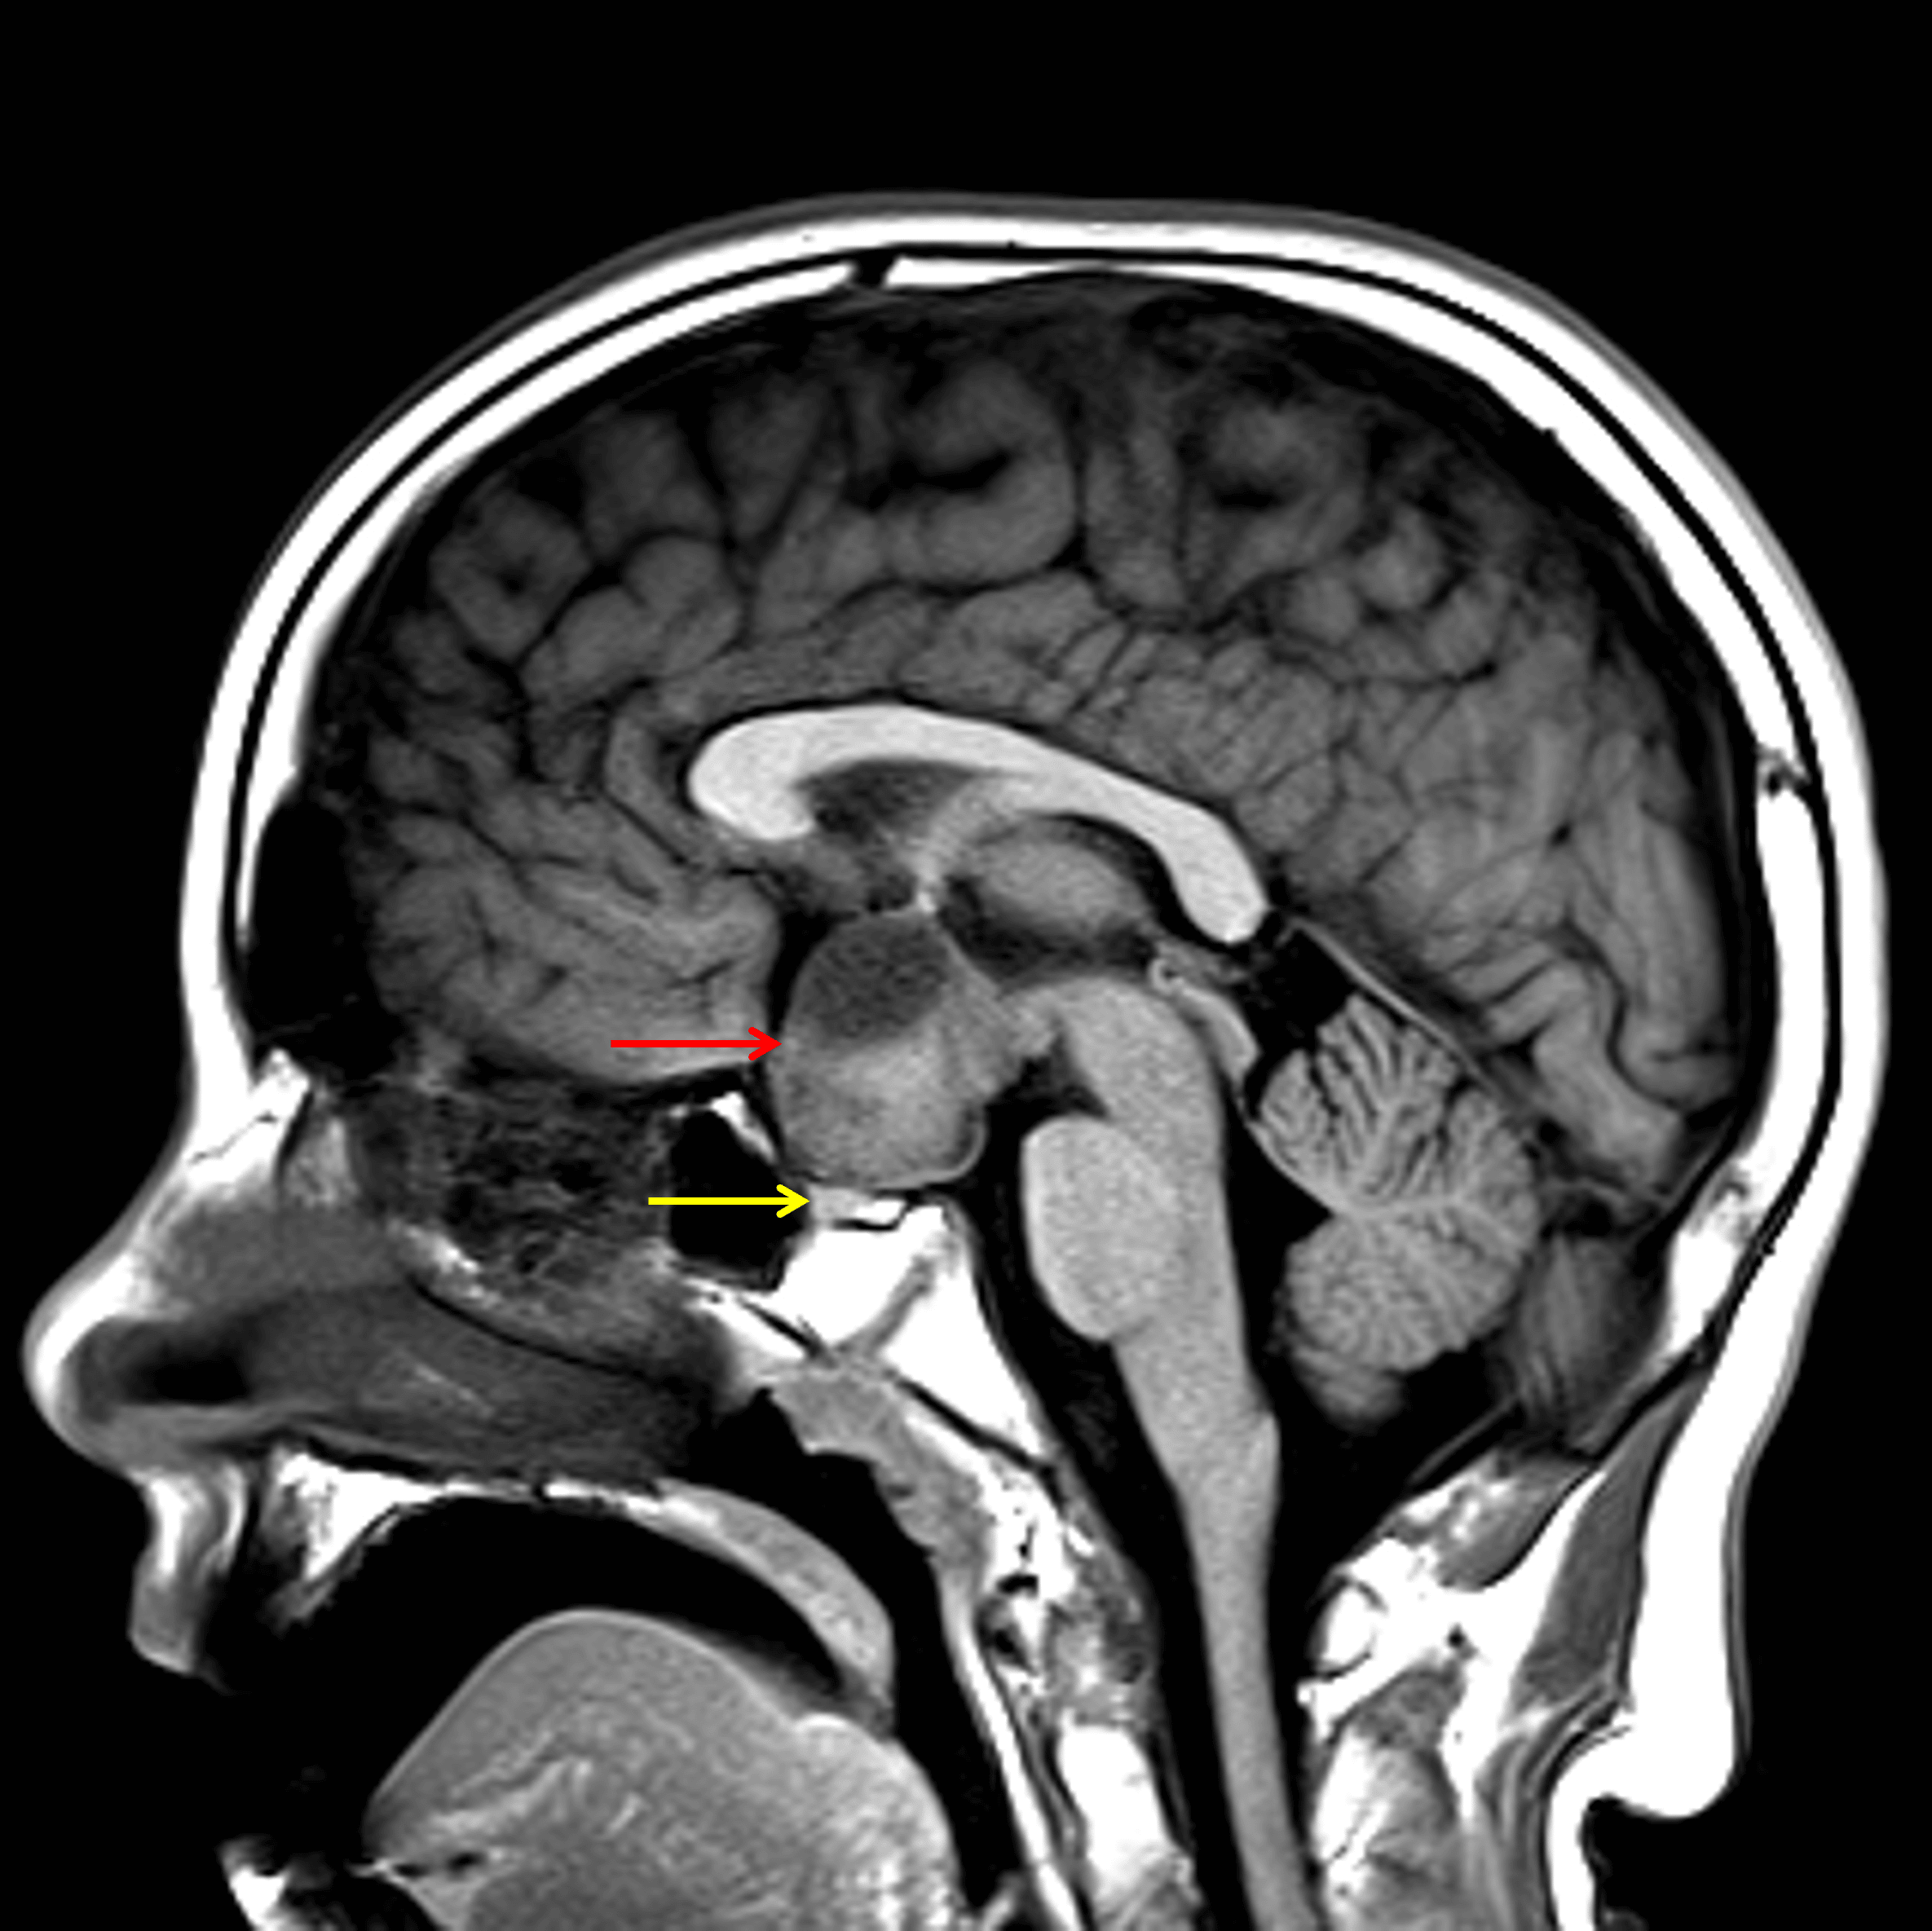

Heterogeneous suprasellar mass (red arrow) which is seen separate from the pituitary gland (yellow arrow).

• Suprasellar mass measuring 3.5 x 2 x 3.3 cm with heterogeneous internal T1 and T2 signal

• The optic chiasm appears to be incorporated within the mass

• The pituitary gland is visualized separate from the mass

• The mass contacts the right A1 ACA segment, both supraclinoid internal carotid arteries, the basilar artery, the posterior communicating arteries, and the P1 segments of both PCAs

• The mass also contacts and deforms the floor of the third ventricle

Optic pathway glioma (pilocytic astrocytoma)